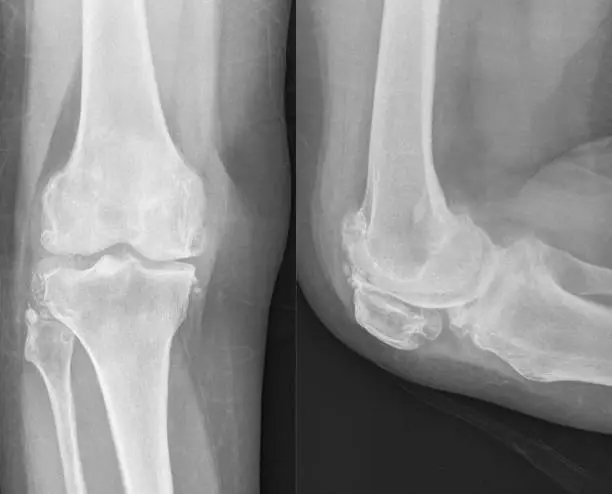

Unlocking Joint Youth: How Inhibiting 15-PGDH Could Redefine Osteoarthritis Treatment Osteoarthritis (OA) silently erodes joint cartilage, turning daily movement into pain for millions. Current options—painkillers, therapy, or knee/hip replacement—manage symptoms but fail to restore lost tissue. A 2025 breakthrough from Stanford changes this narrative by targeting 15-hydroxyprostaglandin dehydrogenase (15-PGDH), an enzyme dubbed a “gerozyme” for […]